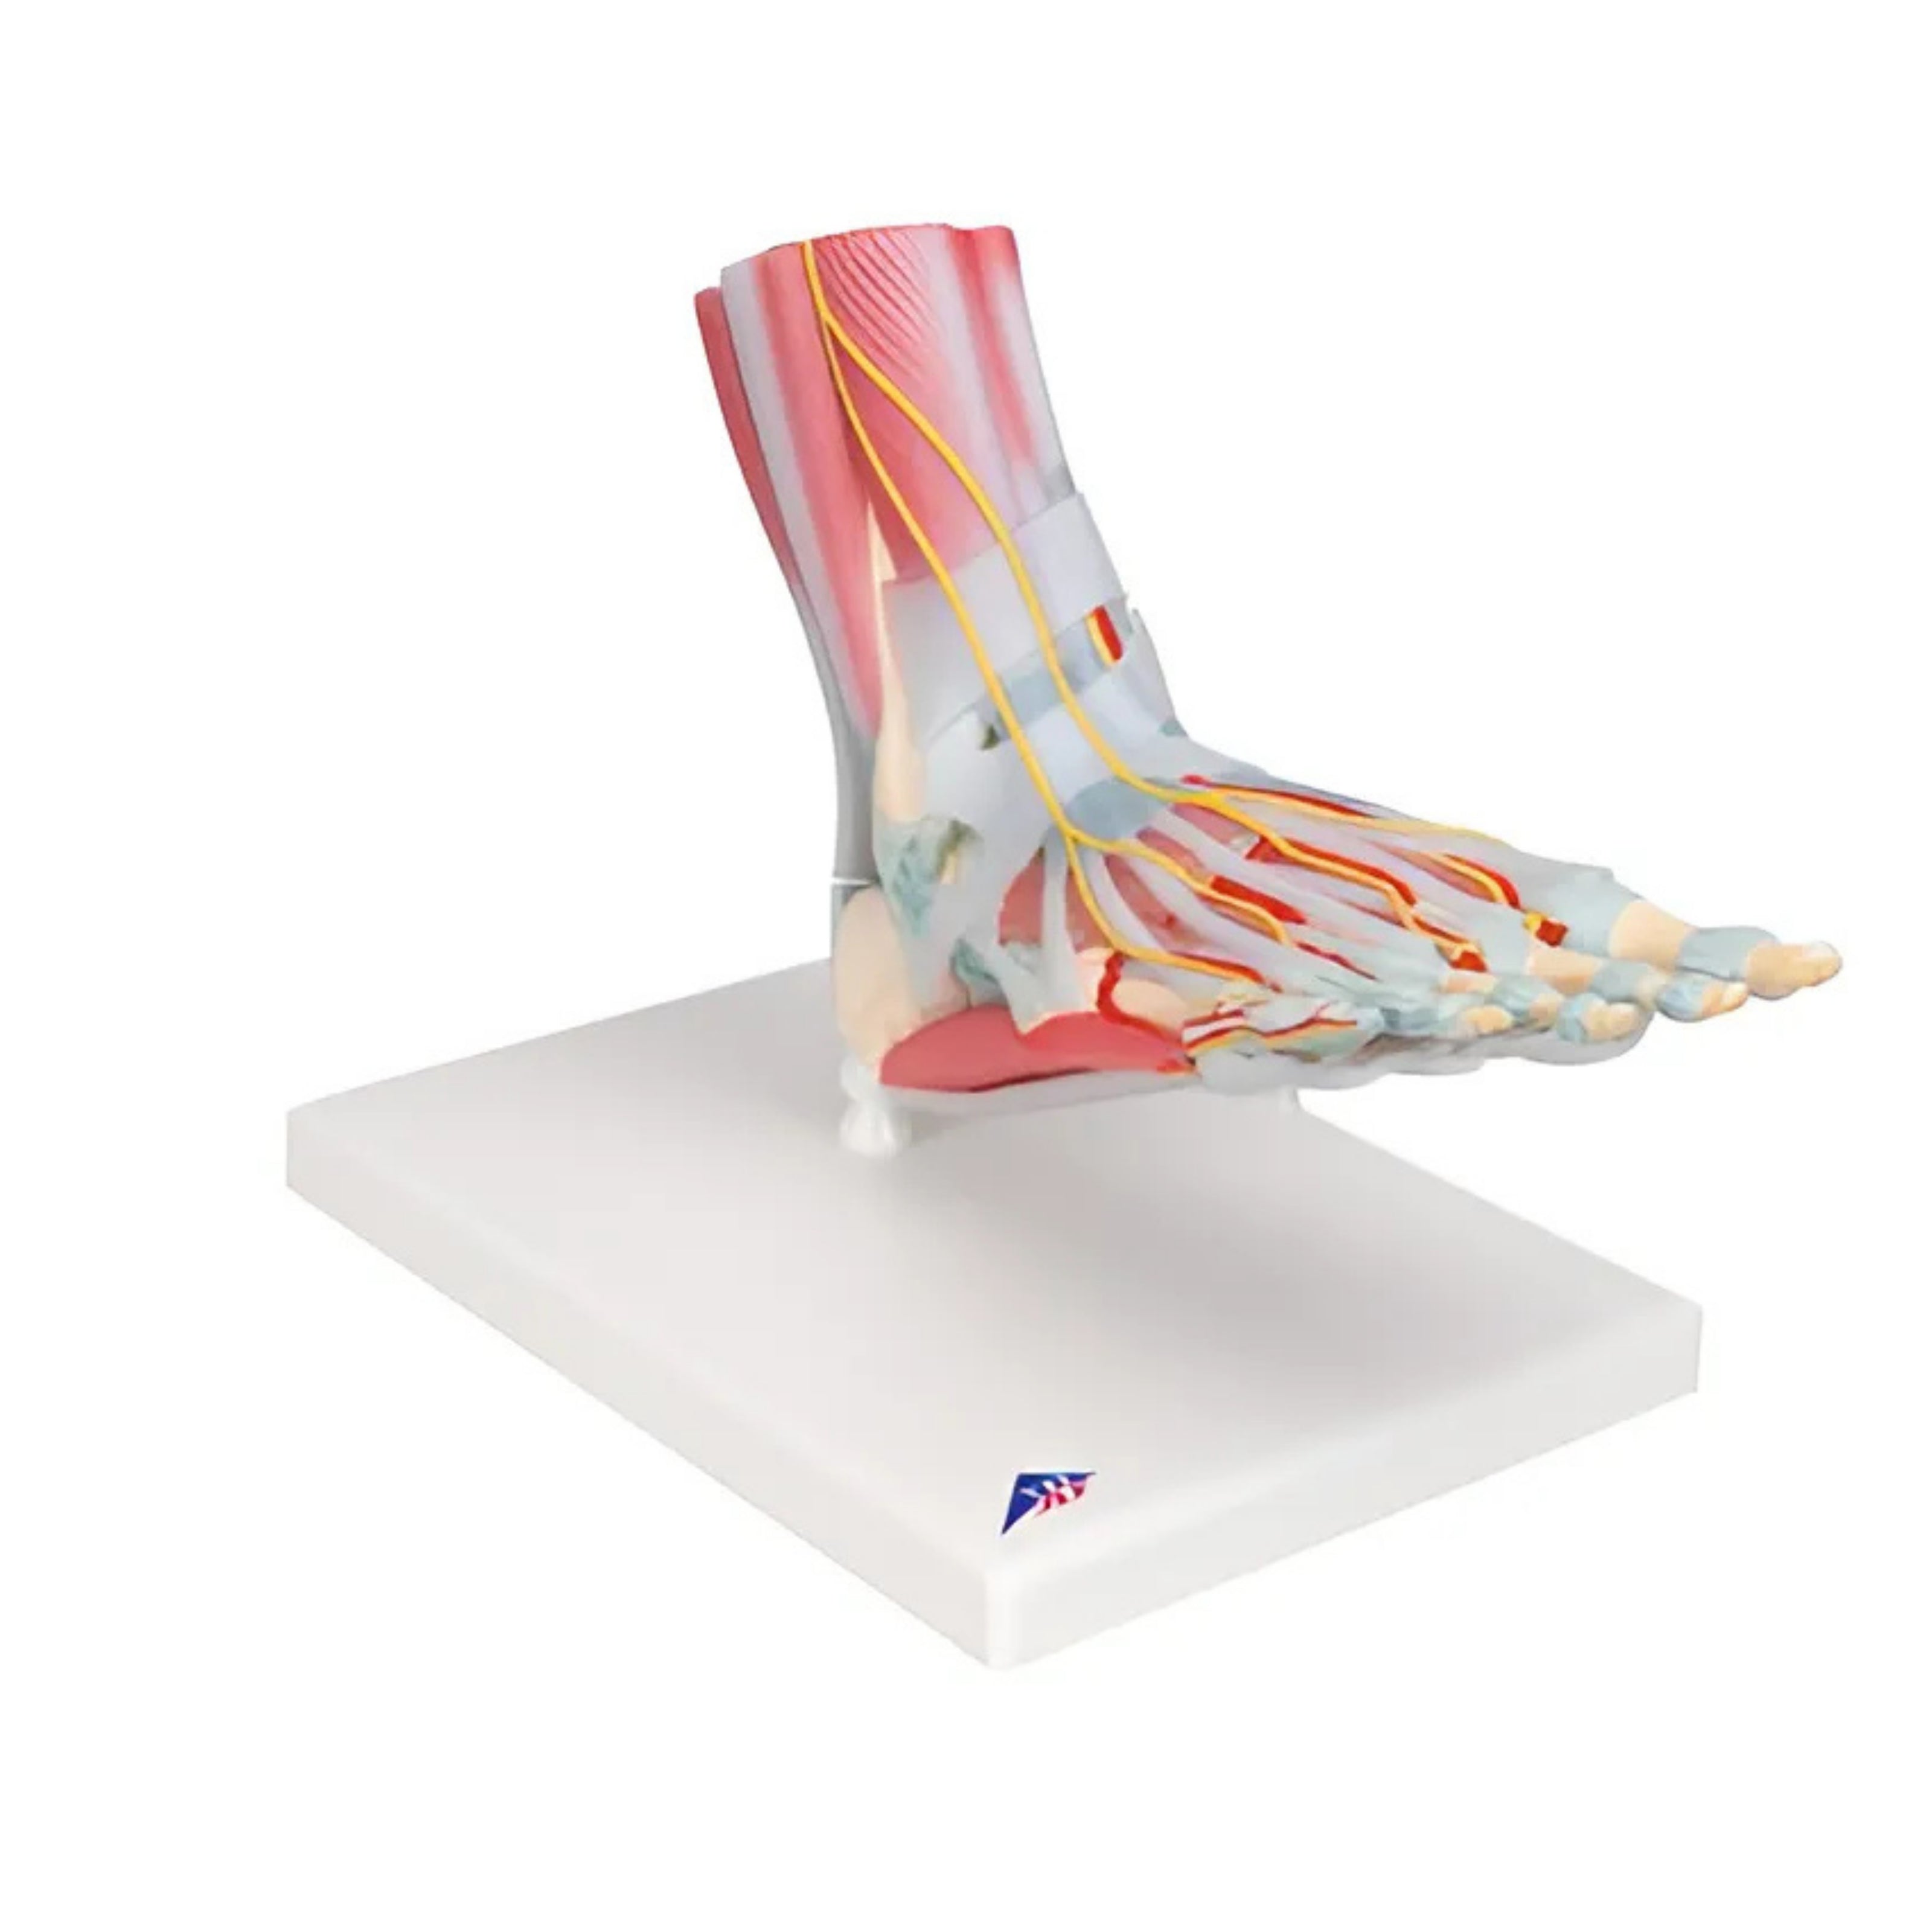

Modelo Anatómico del Esqueleto del Pie con Ligamentos y Músculos - 3B Smart Anatomy

Precio de venta$14,896.38